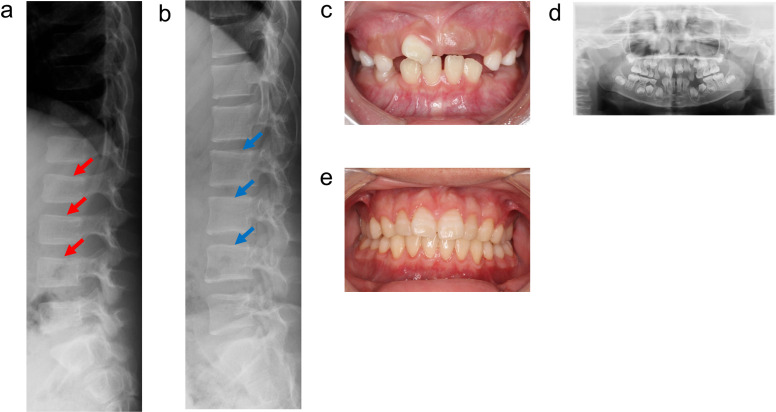

低磷酸症(HPP)是一种遗传性疾病,其特征是由组织非特异性碱性磷酸酶(TNSALP)活性降低引起的骨矿化受损。具体来说,HPP是由编码TNSALP的ALPL基因的功能丧失变体引起的。尽管基因型-表型相关性已被描述,但表型差异已被报道在具有相同变异的患者中,甚至在家庭内。先证者,一名女孩,被怀疑在子宫内有长骨骨折,暗示成骨不完全。出生后未见呼吸障碍;但患者血清碱性磷酸酶水平较低。此外,患者的围产期表现与围产期良性HPP一致,尽管随后骨骼症状恶化。患者的兄弟最初因乳牙过早脱落而怀疑患有牙髓- hpp,后来出现压缩性骨折和骨外症状。两例患者均有相同的ALPL变异,c. 572A>G(;)1559del, p. Glu191Gly(;)Leu520ArgfsTer86;然而,他们的病情严重程度有所不同。同一家族中具有相同基因型的HPP患者可能具有不同的HPP严重程度。在本病例报告中,两名患者均接受了酶替代治疗(ERT),改善了临床症状。因此,对于围产期良性HPP,如果骨骼症状加重,应考虑ERT。此外,应密切监测牙髓- hpp,如果出现骨和骨外症状,应考虑ERT。

Hypophosphatasia (HPP) is a hereditary disorder characterized by impaired bone mineralization caused by decreased tissue-nonspecific alkaline phosphatase (TNSALP) activity. Specifically, HPP is caused by a loss-of-function variant in the ALPL gene encoding TNSALP. Although genotype-phenotype correlations have been described, phenotypic differences have been reported in patients with the same variants, even within families. The proband, a girl, was suspected to have in utero fractures of the long bones, suggestive of osteogenesis imperfecta. No respiratory impairment was observed after birth; however, the patient's serum alkaline phosphatase level was low. In addition, the patient's perinatal findings were consistent with those of perinatal benign HPP, although the bone symptoms subsequently worsened. The patient's brother, initially suspected to have odonto-HPP due to the premature loss of primary teeth, later developed compression fractures and extraosseous symptoms. Both patients had the same ALPL variants, c. 572A>G(;)1559del, p. Glu191Gly(;)Leu520ArgfsTer86; however, the severity of their conditions differed. Patients with HPP with identical genotypes in the same family may have varying severity levels of HPP. In this case report, both patients received enzyme replacement therapy (ERT), which improved the clinical symptoms. Therefore, for perinatal benign HPP, ERT should be considered if bone symptoms worsen. In addition, odonto-HPP should be closely monitored, and ERT should be considered if bone and extraosseous symptoms arise.